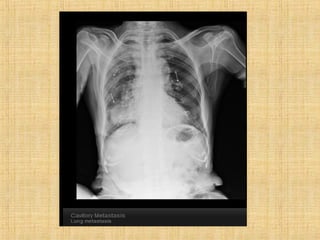

As principais informações do documento são: 1. Discute os padrões de doença pulmonar causados por metástases, incluindo nódulos, espessamento intersticial e obstrução das vias aéreas. 2. A prevalência de metástases pulmonares varia de 30-55% dependendo do tumor primário, e são mais comuns em pacientes acima de 50 anos. 3. Os achados clínicos mais comuns são dispneia, hemoptise e febre, enquanto exames de escarro ou lavado brô